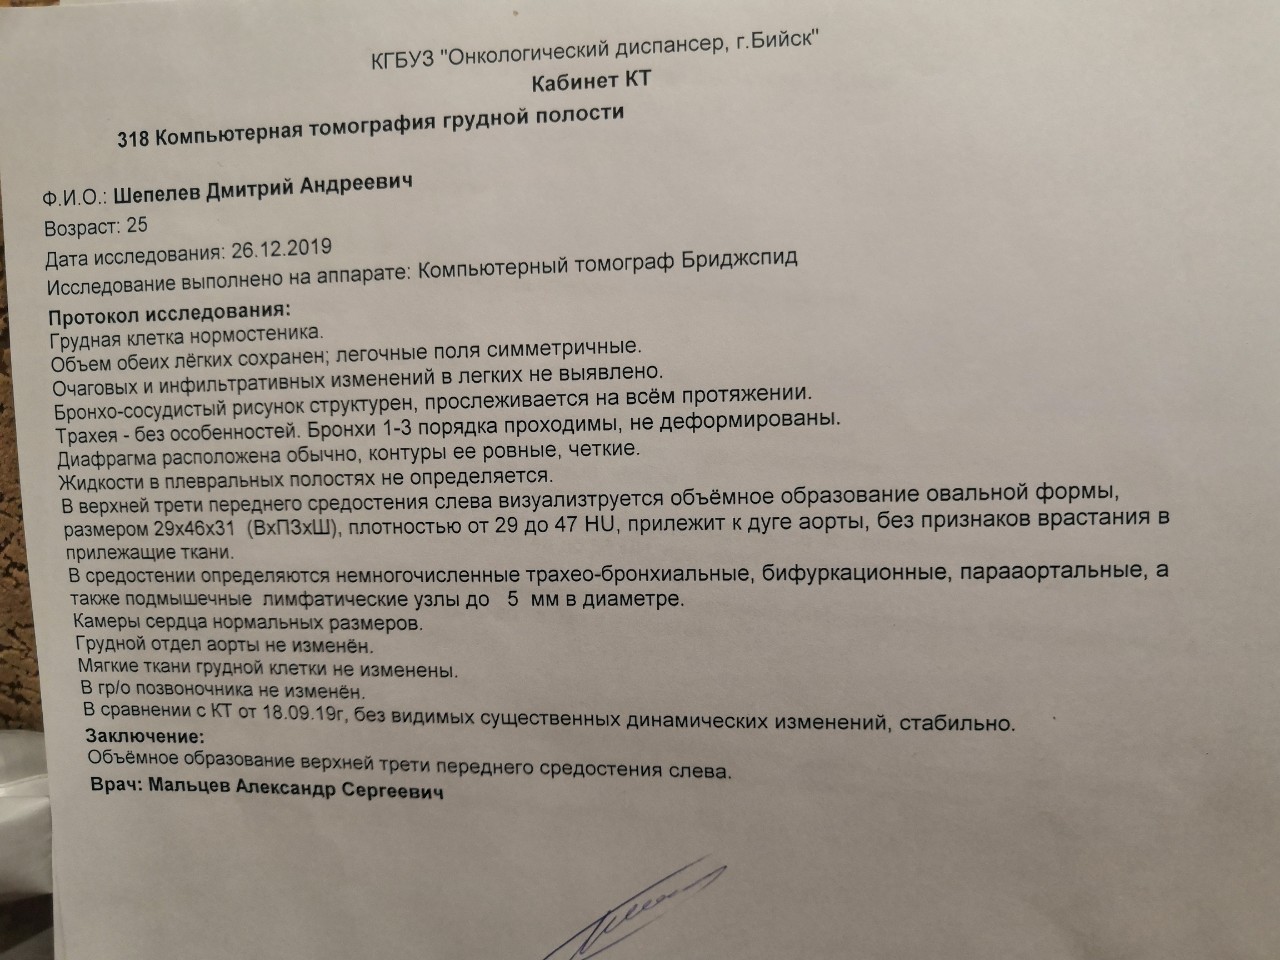

Диагностика лимфомы Ходжкина с помощью ПЭТ и КТ

Раздел: Светлые идеи